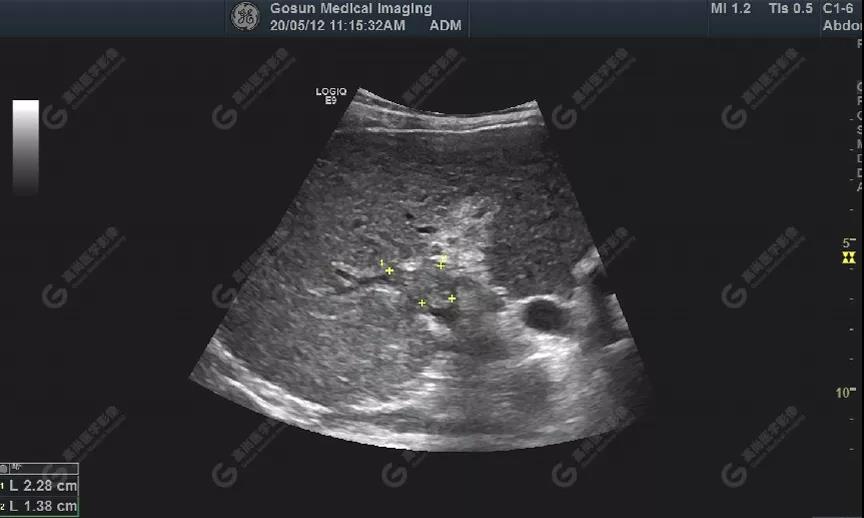

門靜脈右支管腔內(nèi)見大小約23mm×14mm實(shí)性低回聲充填

肝包膜不光滑,實(shí)質(zhì)回聲增粗,不均勻,以右葉顯著,肝內(nèi)可見散在高回聲結(jié)節(jié),最大約7mm×5mm,邊界清,形態(tài)規(guī)則,CDFI顯示高回聲結(jié)節(jié)未見明顯異常血流信號。門靜脈主干內(nèi)徑約14mm,門靜脈右支管腔內(nèi)見實(shí)性低回聲,大小約23mm×14mm,邊界不清,形態(tài)不規(guī)則,局部與肝組織分界不清,CDFI:門靜脈主干血流緩慢,左支血流充盈好,右支血流充盈缺損,低回聲內(nèi)未見明顯血流信號。超聲造影:經(jīng)左側(cè)肘靜脈團(tuán)注超聲造影劑sonovue2.0ml。肝組織開始增強(qiáng)時(shí)間8秒,病灶開始增強(qiáng)時(shí)間11秒,邊界清晰。脈期呈均勻高增強(qiáng),至門脈期和延遲期消退為低增強(qiáng)。延遲期肝S7段局部回聲減低,范圍約82mm×50mm,內(nèi)見一低增強(qiáng)區(qū),范圍約13mm×16mm。